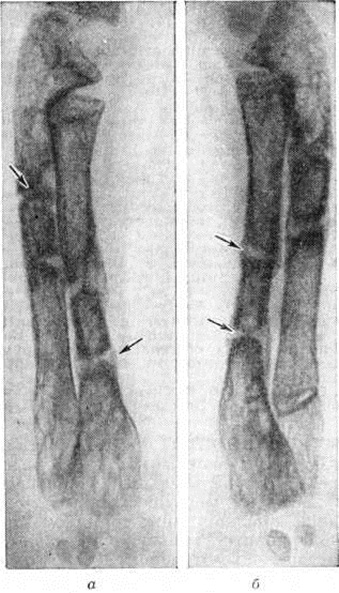

Рис. 1.

Рентгенограмма средней фаланги II пальца руки при хронической почечной недостаточности: субпериостальная резорбция в виде округлых дефектов кортикального слоя кости (указаны стрелками)и уплотнение надкостницы.

Рис. 5.

Рентгенограммы левого (а) и правого (б) предплечий трёхлетнего мальчика с нефрогенной остеопатией: кости предплечий равны по толщине, корковое вещество истончено, резкий остеопороз; стрелками указаны зоны патологической функциональной перестройки.

Метафизы длинных трубчатых костей утолщаются, приобретают чашеобразный вид, что обусловлено задержкой обызвествления остеоидных балок, образующихся вблизи зоны роста (рисунок 5).